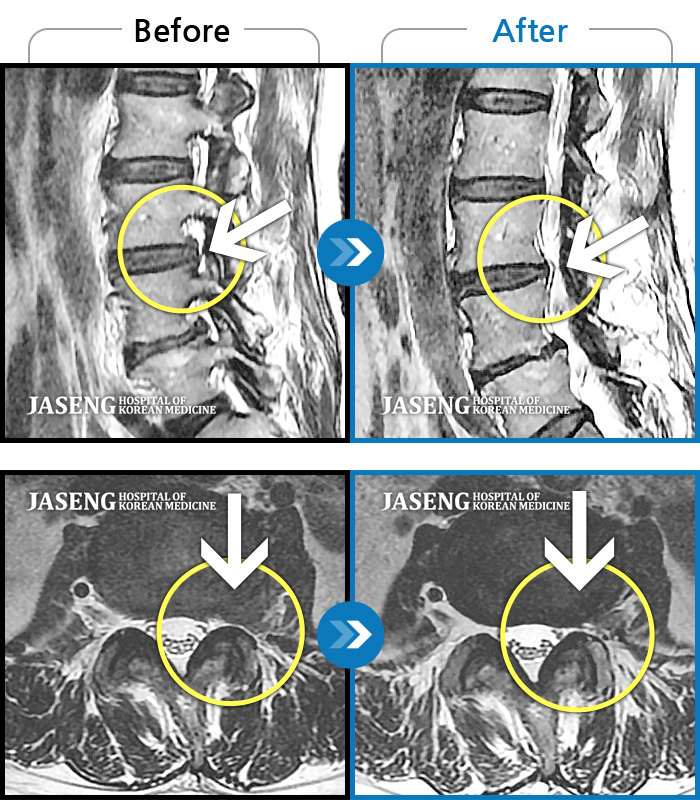

MRI 치료사례

좌측 골반 상연으로 통증과 좌측 대퇴부 통증이 있었다.